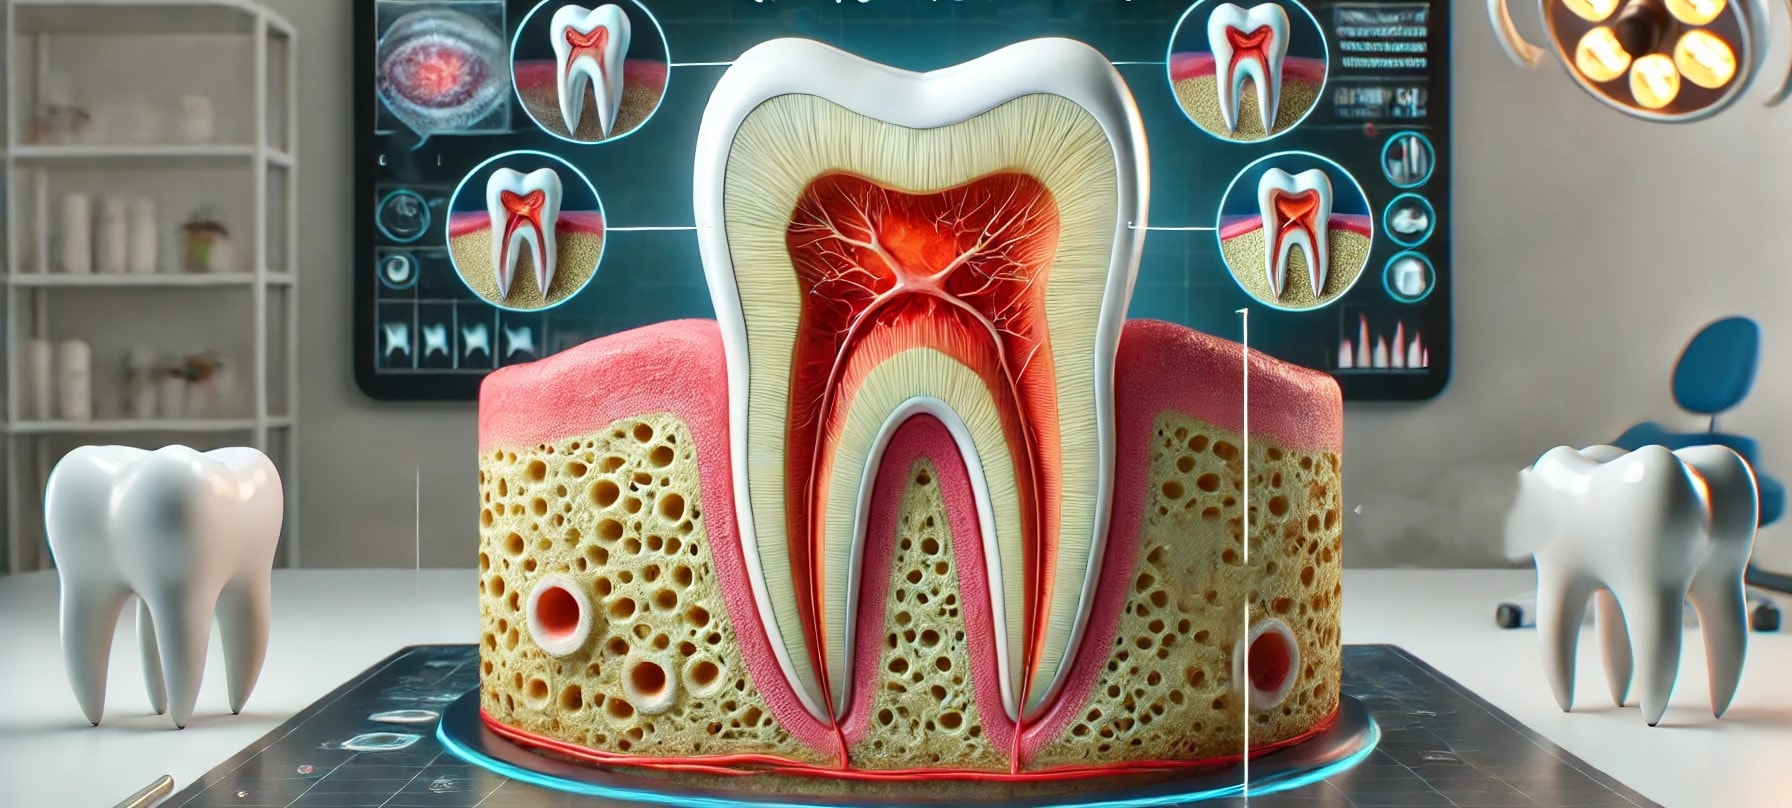

Rotfylling – Pris i 2024. Rotfylling er en vanlig tannbehandling som utføres når det er nødvendig å redde en tann som er skadet av dype hull, infeksjoner, eller traumer. Behandlingen går ut på å fjerne det infiserte eller skadede vevet inne i tannen, rense rotkanalene, og fylle dem med et spesielt materiale for å forhindre videre infeksjon.

Hvordan rotfylling kan redde en tann

Når er rotfylling nødvendig?

Rotfylling av tann innebærer å fjerne det infiserte eller skadede vevet inne i tannen, rense rotkanalene, og deretter fylle dem for å forhindre videre skade. Dette bidrar til å redde en tann som ellers kunne vært trukket.

Hvorfor er rotfylling nødvendig?